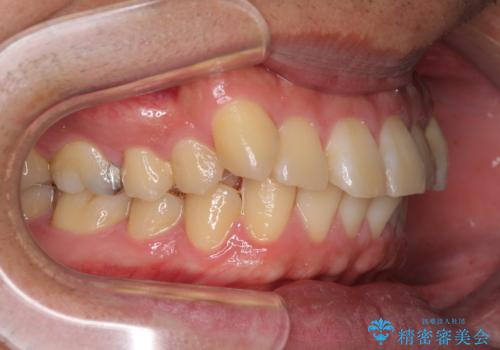

- 前歯のデコボコを気にして来院された患者様です。

当院でインビザライン矯正治療をされている方からのご紹介ということで、インビザラインでの矯正治療をご希望でした。

ワイヤー矯正に比べ来院頻度は低いものの、新幹線での通院のため、やや治療期間が延びることが懸念されました。

配属異動や長時間勤務などによりインビザラインが十分に装着できない期間があり、インビザライン有効期限5年間ギリギリとなってしまいました。